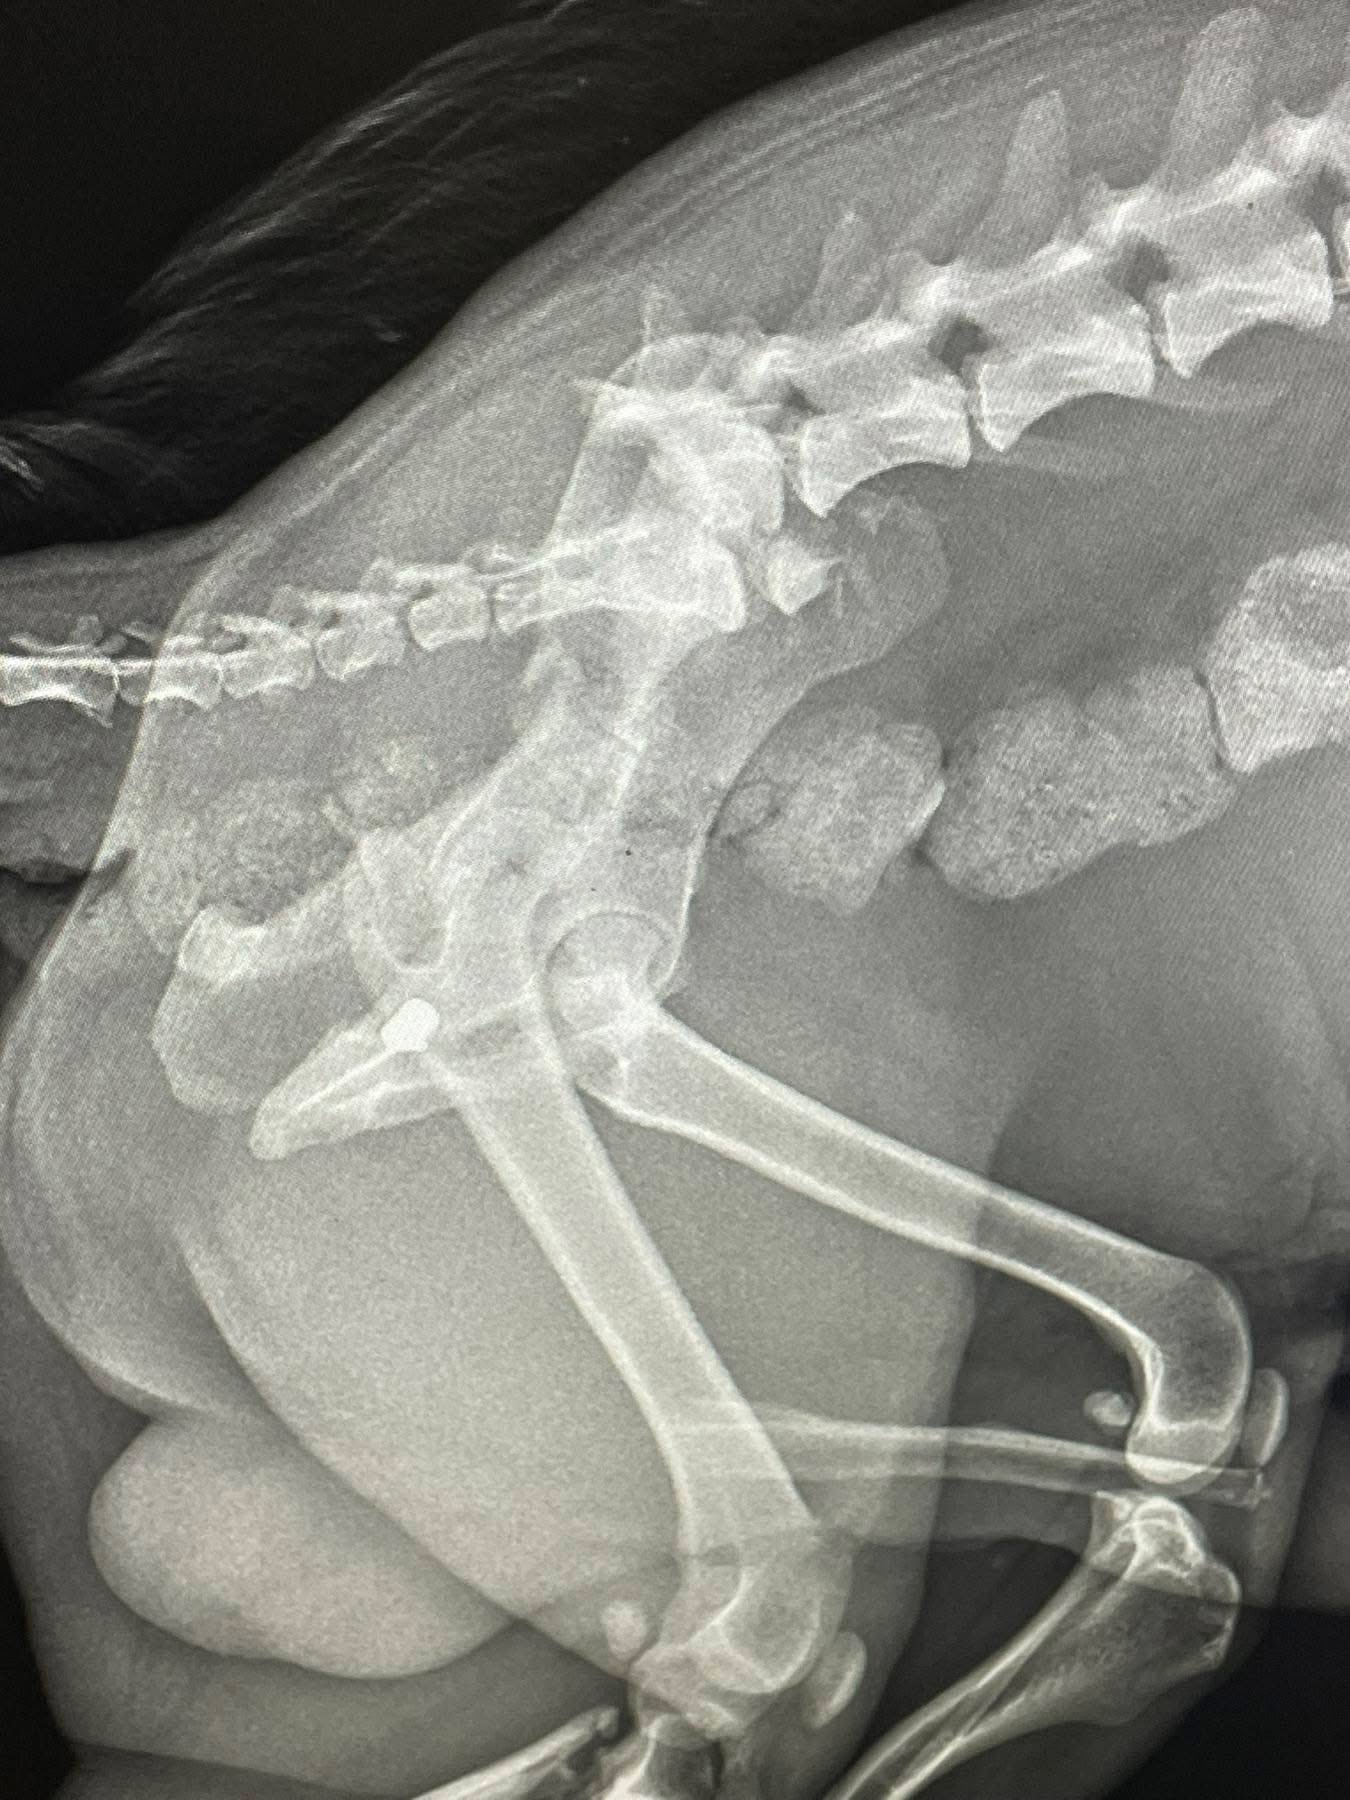

Як зазначено в дописі, огляд та рентген показали наявність у тілі тварини двох куль. Окрім цього, у собаки роздроблені кістки на лапі.